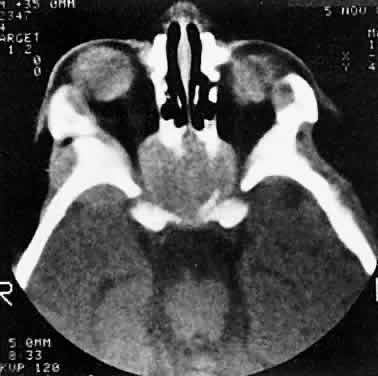

Although no single regimen is appropriate for every child with orbital rhabdomyosarcoma, a sample protocol might include multiple 3-week cycles of chemotherapy, each beginning with intravenous vincristine, actinomycin-D and cyclophosphamide, with vincristine repeated on the eighth and fifteenth days of each cycle. The regimen might include external radiation to a total dosage of 5040 cGy. For poor prognosis cases (e.g., metastatic alveolar rhabdomyosarcoma), newer agents under investigation include ifosfamide, etoposide, and topotecan.2 Having made the diagnosis and contributed to local staging at the time of presentation, the orbital surgeon continues to follow the patient along with the pediatric oncology team. In cases of treatment failure, “salvage” surgery may take the form of orbital exenteration8 or excision of residual tumor combined with brachytherapy.9 Rhabdomyosarcoma underscores the importance of clinical suspicion when dealing with acute proptosis in childhood. Prompt referral to a tertiary center after appropriate imaging is the responsibility of the primary ophthalmologist, family practitioner, or pediatrician who may first encounter the patient. OTHER PRIMARY SARCOMAS Other primary orbital sarcomas may have a relatively abrupt onset of proptosis, although their progression generally is less explosive than that of rhabdomyosarcoma. As with rhabdomyosarcoma, a prompt biopsy is critical for appropriate management. Alveolar soft part sarcoma, an example of this group of lesions, is a rare tumor that may affect the pediatric orbit. In an extensive review of the literature, Sullivan and colleagues10 identified about 50 orbital cases. They noted that the tumor tends to involve the extremities of young adults or the head and neck region of children, with a predilection for the orbit and tongue. A myogenic origin is favored, but there also is evidence for a neural derivation. The findings of imaging studies are nonspecific. Diagnosis depends on the light and elec-tron microscopic demonstration of periodic acid-Schiff-positive, diastase-resistant crystals within the cytoplasm of large polyhedral tumor cells.11 Pediatric patients appear to have a better prognosis than do adults. The currently recommended treatment is local excision of circumscribed primary lesions, with exenteration reserved for diffuse orbital involvement or local recurrence. Radiation therapy may have adjunctive value. Epithelioid sarcoma is a rare tumor that can occur in older children and young adults. Most lesions originate in the distal upper extremities. White and coworkers12 identified two patients; one was a 17-year-old girl with primary epithelioid sarcoma of the orbit. The tumors have both mesenchymal and epithelial histologic qualities and grow in tendon sheaths in a grossly nodular pattern. Treatment strategies have yet to be defined for this rare lesion. NEUROBLASTOMA Neuroblastoma is the most common metastatic orbital lesion in children.13 It represents 10% to 15% of all pediatric malignancies, ranking behind only leukemia and solid central nervous system tumors in frequency. It is a tumor of primitive neuroblastic tissue and, in some respects, is the autonomic nervous system counterpart of retinoblastoma. It usually originates in the adrenal medulla or other retroperitoneal sites but also may arise from any of the sympathetic ganglia in the mediastinum or neck. Neuroblastoma typically afflicts children from 18 months to 3 years of age, although it may be present at birth or may not appear until the midteens. In a review of more than 400 cases of neuroblastoma, Musarella and colleagues14 found the incidence of ophthalmologic signs to be 20%. In almost half of these cases, the ocular symptoms were the presenting complaints. The most common eye signs were related to orbital metastasis. Orbital involvement was bilateral in approximately half of the cases. Characteristic eye findings include proptosis and periorbital ecchymosis. The latter results from hemorrhagic necrosis within a rapidly growing tumor that has outstripped its blood supply. Other eye signs may reflect more distant tumor involvement. Horner's syndrome can result from a primary neuroblastoma in the sympathetic ganglia of the neck or mediastinum or from metastases to either of these regions.13–15 An infantile Horner's syndrome is characterized by hypochromia of the ipsilateral iris. Ocular signs may include opsoclonus, a wild conjugate oscillation of both eyes that may be associated with myoclonus, and truncal ataxia.14 It has been proposed that this complex results from an antibody directed against neuroblastoma antigen, which may cross-react with cerebellar tissue, producing damage in that area.16 Neuroblastomas manufacture catecholamines, which, in sufficient quantity, can produce flushing, systemic hypertension, and diarrhea. Diagnosis is aided by the demonstration of catecholamine metabolites in the urine.17 In cases of suspected neuroblastoma metastatic to the orbit, the primary tumor may be shown by abdominal or thoracic imaging studies. A histologic diagnosis generally is required, however. Orbital soft tissue involvement usually follows extension from bony metastasis (Fig. 3). Therefore, orbital biopsies should be performed extraperiosteally, because the periorbita may still be intact and constitute a relative barrier to tumor extension. Because the histologic differential diagnosis includes other poorly differentiated tumors of childhood, speci-mens should be fixed in both formalin and glutaraldehyde, and fresh tissue also should be submitted. Histologically, neuroblastomas display features commensurate with their degree of differentiation. At the more primitive end of the spectrum are tumors comprising small round cells with minimal cytoplasm. At the other extreme are lesions consisting of large, cytoplasm-rich elements resembling ganglion cells. It has been proposed that neuroblastomas having undergone spontaneous clinical regression have evolved into benign ganglioneuromas.18 Homer-Wright pseudorosettes characteristically present in well-differentiated primary neuroblastomas and are rarely, if ever, found within orbital metastases. In poorly differentiated tumors, electron microscopy may be required to show neurosecretory granules containing catecholamines. The rapidly advancing field of immunohistochemistry also has contributed to diagnosis and prognostic assessment in neuroblastoma.19 As with rhabdomyosarcoma, the choice of treatment protocols for neuroblastoma is based on tumor staging and the multiple prognostic factors that have been identified in large cooperative trials. Approximately 25% of children with newly diagnosed neuroblastoma present with nonmetastatic and localized disease.19 This group has a 98% survival with surgery alone as primary therapy. However, children with localized disease who have amplification of the MYCN oncogene or who are 2 years of age or older with either unfavorable histopathology or positive lymph nodes are at greater risk of death. Other negative factors include elevated serum ferritin and elevated serum neuron-specific enolase. The majority of children with neuroblastoma have metastatic disease at diagnosis.20 In order of frequency, the most common sites are bone marrow, bone, lymph nodes, liver, intracranial and orbital sites, lung, and central nervous system. The metastatic pattern differs with age. Patients younger than 1 year are more likely to have liver or skin metastases at diagnosis and less likely to have bone and bone marrow metastases at diagnosis than do patients age 1 year or older. Among children with metastases at diagnosis, event-free survival is decreased in patients with bone, bone marrow, central nervous system, intracranial/orbital, lung and pleural metastases, and improved in those with liver and skin metastases. Depending on tumor staging and risk factors, treatment protocols may include surgical resection of the primary tumor, combination chemotherapy (cisplatin, cyclophosphamide, doxorubicin, and etoposide) of varying dose-intensity, and myeloablative therapy with autologous purged bone marrow transplantation.19 OTHER METASTATIC LESIONS Orbital metastases from other solid pediatric tumors are less common. Of these, Ewing's sarcoma accounts for the majority, and Wilms' tumor is responsible for an extremely small number of cases.13,21 Ewing's sarcoma accounts for approximately 10% of tumors that metastasize to the pediatric orbit. Albert and colleagues13 noted orbital involvement in five of 12 patients with Ewing's sarcoma. In all patients, the orbital metastases were unilateral and were clinically noted several months after diagnosis of the primary lesion. Ewing's sarcoma usually arises within the medullary canals of the bones of the trunk or extremities. Unlike neuroblastoma, its peak incidence is in late childhood and adolescence. Ewing's sarcoma and malignant peripheral neuroectodermal tumor (PNET) are closely related, but are distinguished by the microscopic and immunohistochemical findings of greater neuroectodermal differentiation (e.g., rosette formation) in the latter lesion.22,23 Although earlier studies suggested a poorer prognosis in PNET than in Ewing's sarcoma, more recent work showed no difference in clinical outcome.24 Radiation therapy, surgery, and chemotherapy are used in management. The principal adverse prognostic factor is metastasis at diagnosis. In a European study of 975 patients enrolled from 1977 to 1993, the 5-year relapse-free survival of patients without metastases at diagnosis was 55% compared to 22% for patients with metastases at diagnosis.25 During the second 8 years of the study, these figures were 60% and 30%, respectively, indicating continued outcome improvement. Wilms' tumor (nephroblastoma) arises from embryonic elements within the kidney. Although it affects children almost as frequently as neuroblastoma and can metastasize extensively to other sites, orbital lesions have been rarely described.21,26 Reports have concerned children younger than 3 years of age. As of 1999, the overall survival rate for Wilms' tumor was 90%.27 Most patients have favorable histology (nonanaplastic or focally anaplastic tumors), and survive after preoperative chemotherapy and nephrectomy.27–29 However, poor outcomes are associated with diffuse anaplasia, chromosomal loss on 1p and 16q, diploidy, lung or liver metastases, major tumor spillage during resection, remote lymph node involvement, and bilateral tumors. ACUTE LEUKEMIA Leukemia is the most common malignancy in childhood, and nearly all pediatric leukemias are acute rather than chronic. The lymphoblastic variety is approximately four times more common than the myelogenous form. Leukemic cells frequently lodge in the eye and adnexa, and bilateral involvement is common.30 Proptosis occurs less often than intraocular or optic nerve complications and may result from a combination of local tumefaction and hemorrhage. Most ophthalmic complications of leukemia are associated with the acute lymphoblastic rather than the myelogenous form of disease. Orbital infiltration may occur in either condition but is disproportionately more common in acute myelogenous leukemia (AML).31 In the latter disorder, orbital tumefactions (myeloid or granulocytic sarcomas) may curiously precede bone marrow and peripheral blood evidence of leukemia by several months.32–34 For this reason, ophthalmologists may be the first to diagnose this systemic disease. The correct early diagnosis is important, because chemotherapy may be more effective if initiated before the leukemic phase develops. Extramedullary deposits of primitive myeloblasts may occur at any time in the course of acute myeloid leukemia. The growths have been termed chloromas because of a greenish hue imparted by the enzyme myeloperoxidase within the tumor cells. This discoloration fades on exposure to the air and is therefore an inconstant finding at the time of histopathologic preparation and diagnosis.35 Granulocytic or myeloid sarcoma is considered a more appropriate term and is preferred. Favored sites of involvement are the bones and periosteum of the skull, including those of the orbit. Granulocytic sarcomas also may occur in the orbital soft tissues and the eyelids. Zimmerman and Font32 studied 33 granulocytic sarcomas of the orbit and eyelids, 29 of which were examined by biopsy before a diagnosis of leukemia had been established. In most of their cases, hematologic investigation confirmed the systemic process soon after the sarcomas were identified. In some cases, however, intervals of 4 to 15 months elapsed before leukemia was diagnosed by bone marrow and peripheral blood examination. Because of these delays and because the lesions can be histologically ambiguous, granulocytic sarcomas may be misdiagnosed as independent, primary sarcomas or as histiocytic lymphomas. Granulocytic sarcomas of the orbit may be bilateral in 10% to 45% of cases.32,33 Hemorrhage occurs frequently, and eyelid ecchymosis may be a pre-senting sign. Most patients are affected in the first decade of life, and males are involved more often than females. The majority of cases in the series cited were derived from Asia, Africa, or the South Pacific, and, interestingly, granulocytic sarcoma was the second most common cause of proptosis in Uganda after Burkitt's lymphoma. Findings on imaging studies are nonspecific. The diagnosis depends on biopsy results.36 As in other pediatric tumors, light microscopy may yield ambiguous findings, and immunohistochemical stains and electron microscopy are helpful. Granulocytic sarcomas are composed of large mononuclear cells that resemble histiocytes. Diagnosis may be difficult when immature myeloblasts dominate the histologic picture, and evidence of granulocytic differentiation is minimal. Diagnosis is aided in these cases by the Leder stain, which indicates esterase activity and cellular differentiation in a myelocytic direction. In addition, the immunohistochemical stain for lysozyme is positive in 60% to 89% of cases. In patients in whom both the Leder and lysozyme stains are negative, the monoclonal antibody MAC387 may establish the diagnosis.34 Electron microscopy may show early granule formation. Compared to progress in pediatric acute lympho-blastic leukemia during the past 2 decades, improvement in the cure rate of children with AML has been modest.37 Among children treated with chemotherapy alone, about 40% are long-term survivors. Prognosis improves with bone marrow transplants from histocompatible sibling donors early in the first remission. Molecular genetic advances are expected to improve therapeutic strategies. BURKITT'S LYMPHOMA Although it is a rare cause of proptosis in the Western hemisphere, Burkitt's lymphoma deserves attention because of its distinctive epidemiologic and clinical features. The tumor occurs endemically within certain geographic and climatic boundaries in East Africa. It is the most common pediatric orbital tumor in Uganda, accounting for almost 50% of cases.38 The average age of presentation is 7 years, with a range from 3 to 15 years. Large extranodal tumors occur in the bones of the jaw and the abdominal viscera. Unilateral or bilateral proptosis is present in 20% of cases and usually results from maxillary extension. The progression of proptosis may be explosive. Burkitt's lymphoma has a doubling time that may be as brief as 24 hours, ranking it as the fastest-growing tumor in humans.39 Endemic African cases have been linked to the Epstein-Barr virus and to a t(8;14q) chromosomal translocation, suggesting an interaction between environmental factors and host susceptibility. Sporadic North American cases have a less-definitive viral association. These patients differ clinically in their age of presentation (mean, 11 years) and in the usual site of tumor origin (intra-abdominal lymphoid tissue).40,41 Involvement of the facial bones and orbit is less common in the North American cases, but invasion of the orbit from the sinuses may occur42,43 (Fig. 4).